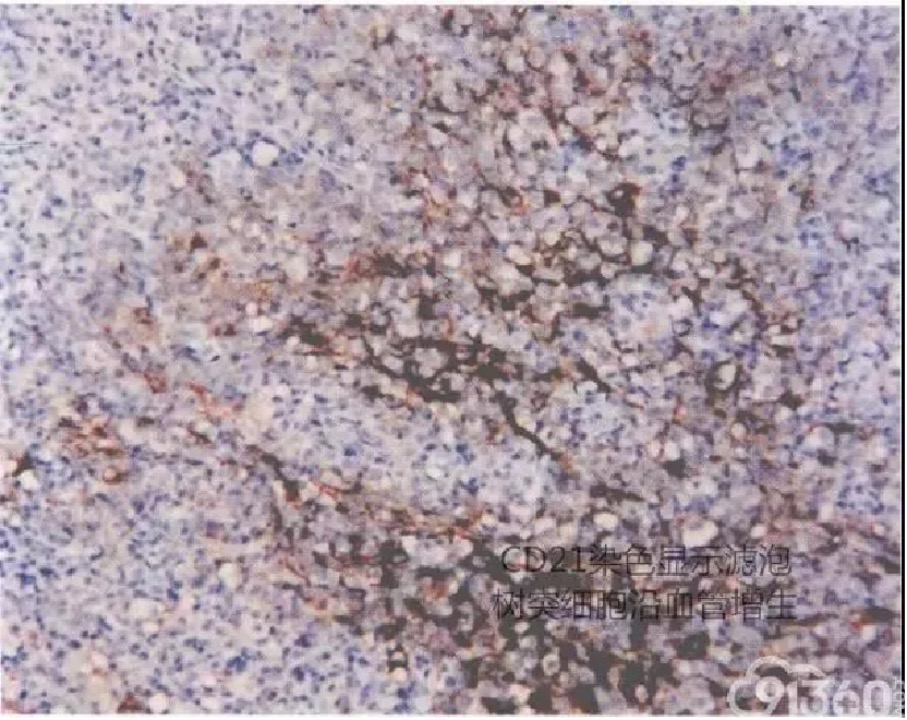

瘤细胞表达T细胞分化抗原,如CD2,CD3和CD5。多数病例之瘤细胞为CD4表型。其肿瘤细胞特征地表达滤泡辅助T细胞标记,如CXCL13,CD10和PD-1。CD21染色显示滤泡外树突状网状细胞主要沿高内皮血管呈丛状增生,并勾勒出生发中心的轮廓。